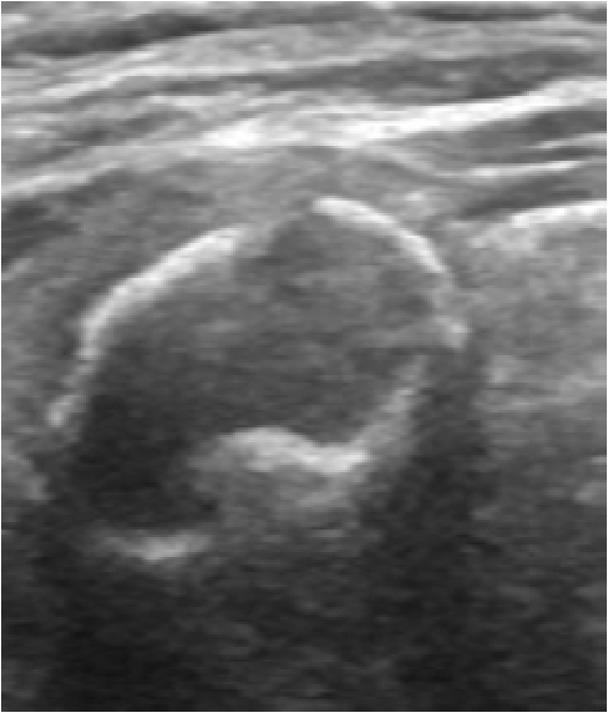

By definition, a spongiform nodule is one that is composed of >50% of small cystic spaces that are evenly distributed throughout the nodule – this appearance resembles a sponge (Fig. 7)(3). Intermediate nodules that do not meet this criterion but show a <80% solid volume should be described as being of mixed cystic and solid composition. When echogenic foci are found in a spongi-form nodule, these are not considered as PEF and should be ignored(4).

Fig. 7

Greyscale sonographic images of: A. spongiform nodule and B. a mixed cystic and solid nodule. Compared to (B), the cystic spaces are smaller and more evenly distributed (A)